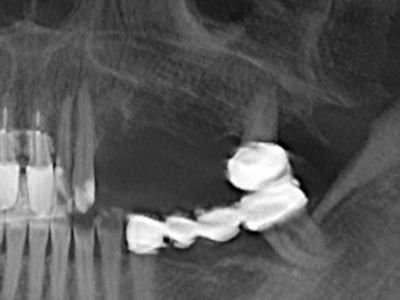

Когато се извършват хирургични процедури върху кост в непосредствена близост до чувствителни структури като кръвоносни съдове или нерви, ротиращите инструменти създават значителен риск за ятрогенно нараняване. Пиезоелектрическите апарати могат да бъдат от помощ при препарация на костно покритие и отстраняване на твърда кост близо до нерви, особено за оголване на нервите след ятрогенно нараняване, както и по време на латерализация на нервите за резекционни и реконструктивни процедури или поставяне на имплант (Фиг. 17-20). Лекият контакт между пиезонакрайника и нерва по принцип не води до нараняване, но ако действате непредпазливо с трионообразни движения или приставки за остатъчен костен субстрат, може да причините временно или перманентно увреждане на нерва. Въпреки това, рискът от увреждане се счита за много по-малък, отколкото при употреба на триони или ротиращи инструменти (Pereira, Gealh et al. 2014).

Както е показано в миналото, всяка костна хирургия представлява възможна индикация за пиезохирургия. По този начин, за препарацията на подвижни сегменти в остеогенеза (Фиг. 23-25) и остеотомия се използват специални накрайници, без да се застрашава снабдяването с кръв в кресталната зона, което е от съществено значение за успеха и на двете техники (Gonzalez-Garcia, Diniz-Freitas et al. 2008).